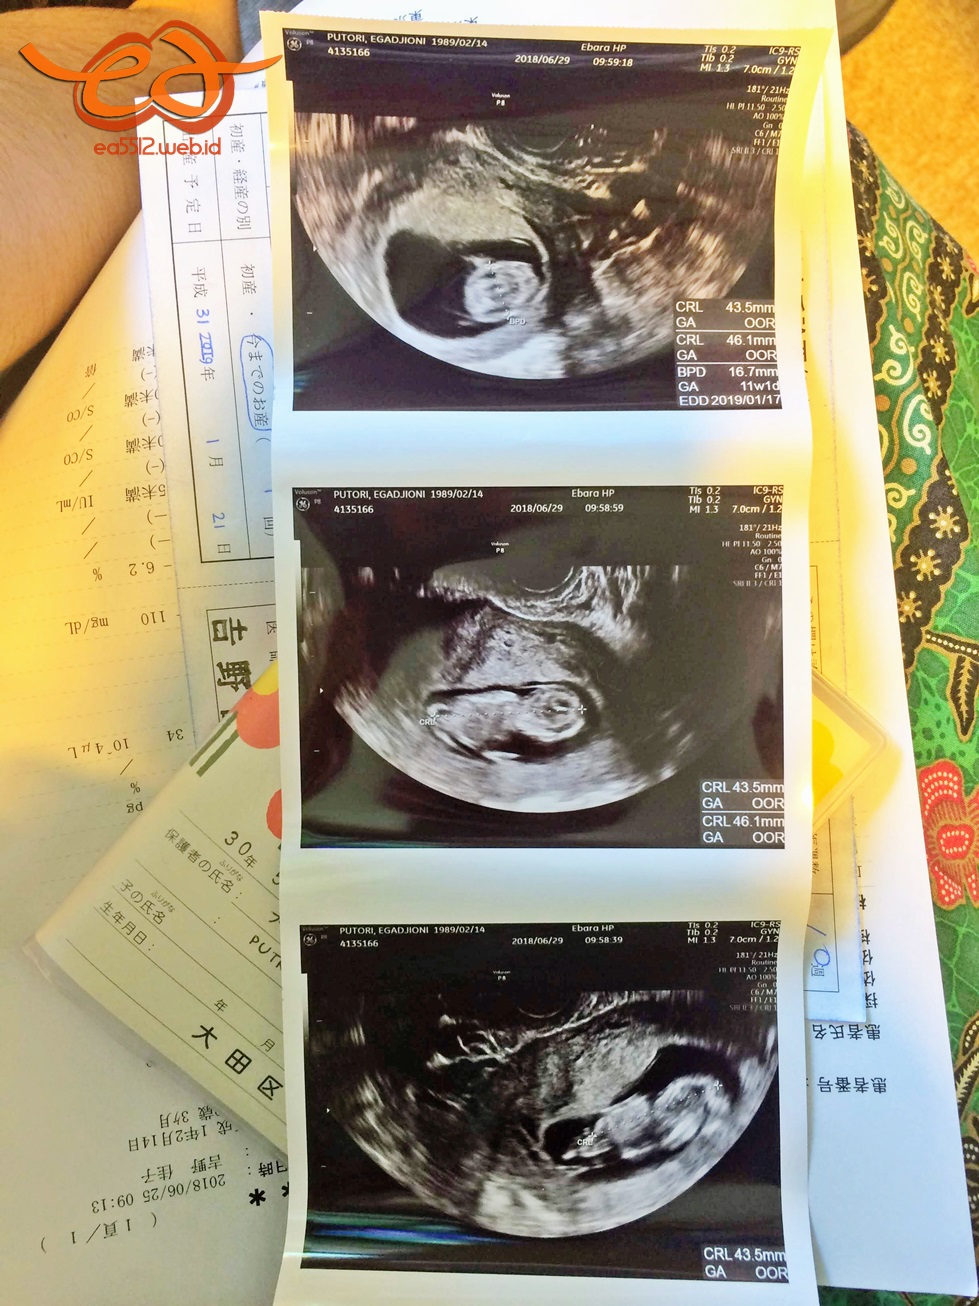

Ultrasound pictures which show the transformation of gestational sac inside my womb: [BEFORE] empty + no fetal pole + no yolk [AFTER] fetus + heartbeat.As this post was written down, the baby aged 14 weeks and had another ultrasound check at 11 weeks.

Hingga hari ini, si bayi udah dicek sekali lagi lewat transvaginal ultrasound dua minggu setelahnya di usia yang menurut perhitungan adalah 10 minggu tapi ternyata jadi 11 minggu sehingga HPL (Hari Perkiraan Lahir) pun sudah tiga kali berubah. Setelah itu, di trimester kedua ini, pemeriksaan memasuki masa 4 minggu sekali. Nanti di trimester ketiga, kontrol akan kembali ke siklus 2 minggu sekali.